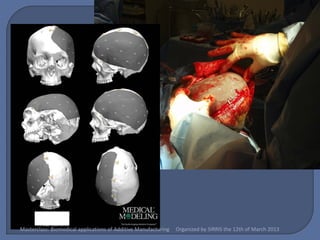

   Methods & Materials:

•    Computed Tomography (CT) scans are obtained

relevant bony structures segmented using Mimics

(Materialise NV).

•    The implant is designed using 3Matic (Materialise NV)

or Freeform Plus (Sensable Technologies)

•    Built in an ARCAM A-1, using Electron Beam Melting of

Ti6Al4V, medical grade titanium alloy.

•    The resultant three dimensional mesh is 3-4mm in

thickness, and has fixation plates integrated.

•    Sterilizable using standard steam autoclave

techniques.